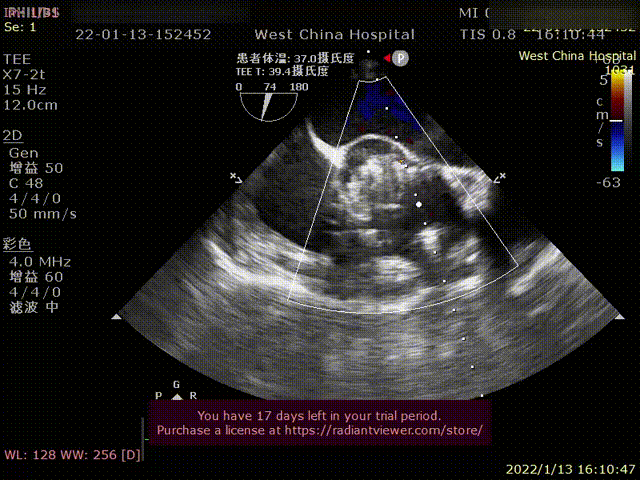

术前超声影像